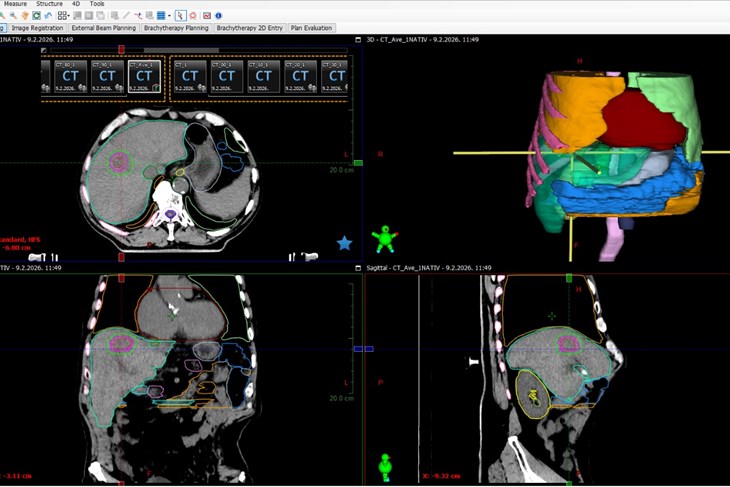

Klinika za tumore KBC-a Rijeka prva je u Hrvatskoj uvela stereotaksijsku radioterapiju jetre (SBRT), jednu od najnaprednijih i tehnički najzahtjevnijih metoda liječenja metastaza i primarnih tumora.

Ovime je postala prva ustanova u javnom zdravstvu koja provodi ovaj zahvat. Metoda predstavlja novi iskorak, jer nakon nedavne uspješne stereotaksije mozga i pluća, uvođenjem ovog – najkompleksnijeg SBRT zahvata, sada je u Rijeci moguće napraviti stereotaksiju na lezijama cijelog tijela.

Stereotaksijska radioterapija (SBRT) jetre danas predstavlja jednu od najnaprednijih i najpreciznijih metoda liječenja malignih promjena jetre (bilo metastaza  ili primarnog tumora jetre). SBRT jetre je tehnika kojom se u malom broju frakcija (najčešće 3–5) isporučuju visoke biološki učinkovite doze zračenja s milimetarskom preciznošću, uz strogu kontrolu položaja tumora, kompenzaciju pokreta uzrokovanih disanjem te uz maksimalnu zaštitu zdravog tkiva jetre.

Jetra je vitalni organ jer bez nje organizam ne može preživjeti. Obavlja više od 500 različitih funkcija koje su ključne za život, radi toga i njene respiratorne pomičnosti, SBRT jetre predstavlja najkompleksniji oblik stereotaktične radiokirurgije. Tijekom planiranja zračenja metastaze ili tumora jetre nužno je voditi brigu o funkciji jetre, te o preostalom zdravom parenhimu jetre koji će moći preuzeti sve potrebne funkcije.